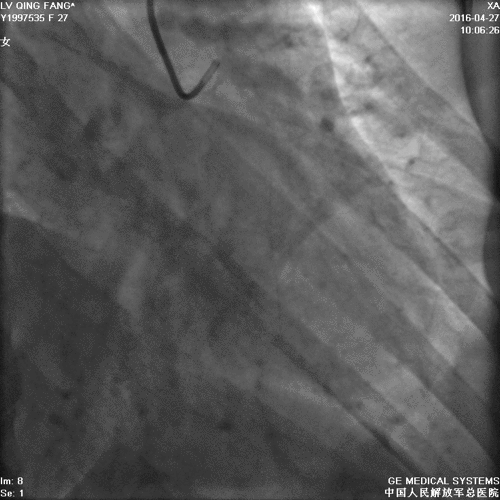

造影

PCI